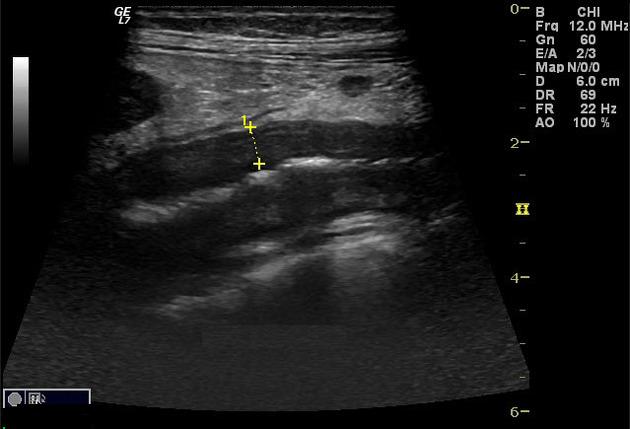

dilate .Aspect echographie percutanee

du colon dans maladie de Crohn est image epaissisement de la

parietale du colon et image de complication abcesde de la

paroi du colon .

Aspect ecographique une abces entre deux anses du

grele dans une maladie de Crohn . En haute de

frequence on peut voyait image de epaissisement de

la paroi du colon ou ileon terminale . |